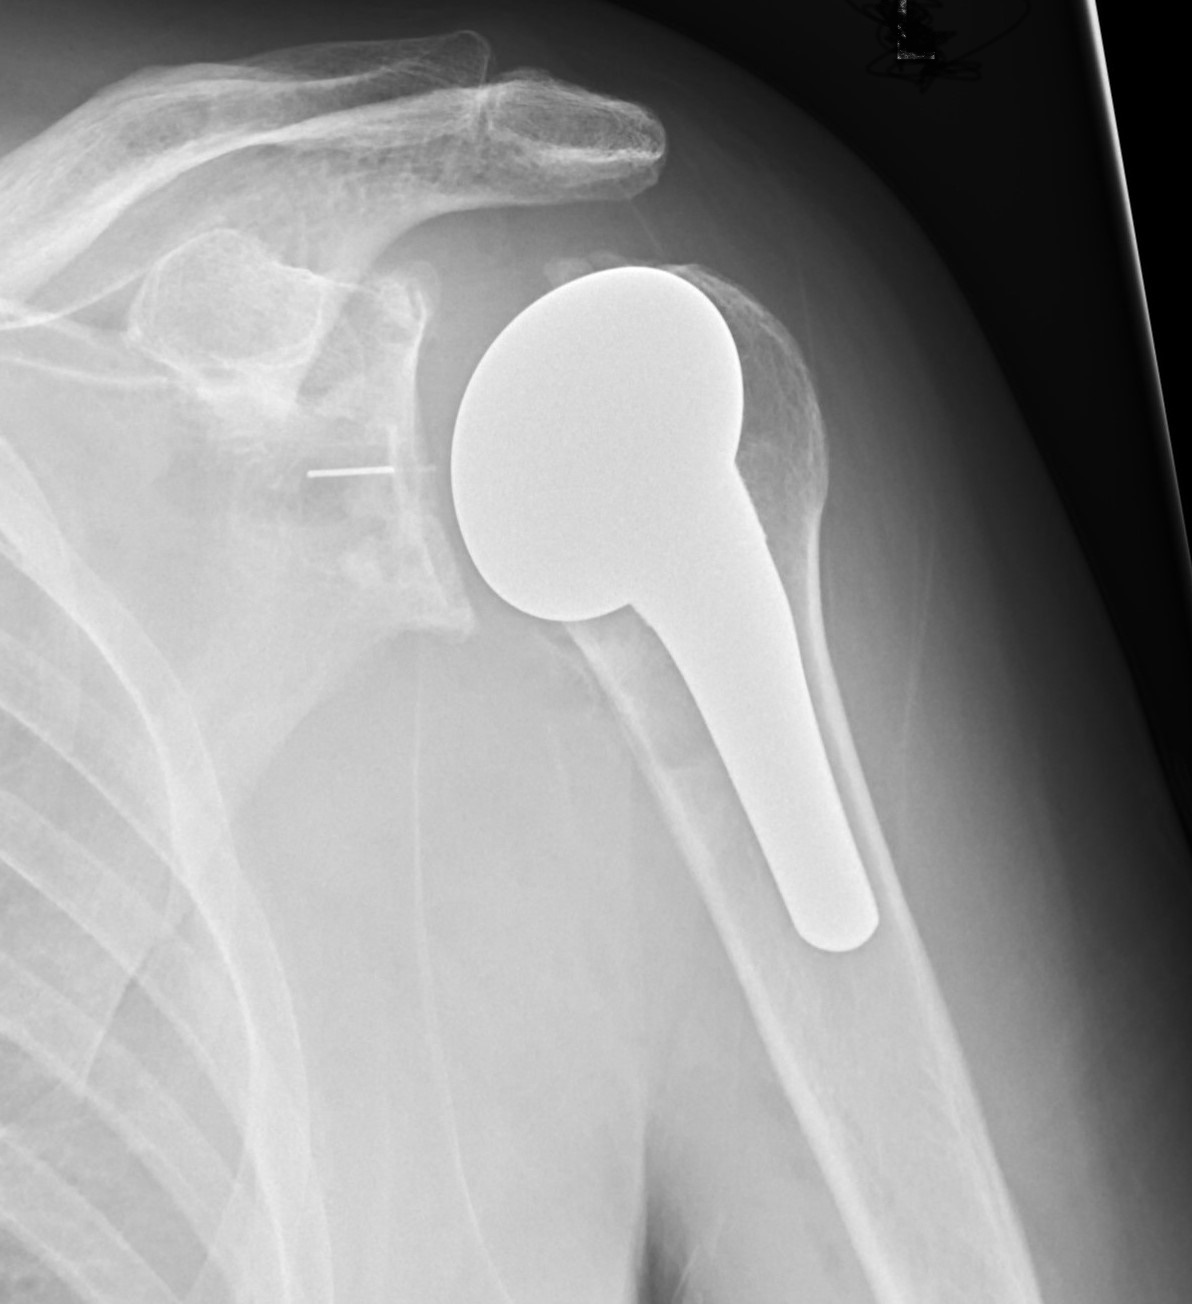

Post operative x ray of an anatomic total shoulder replacement